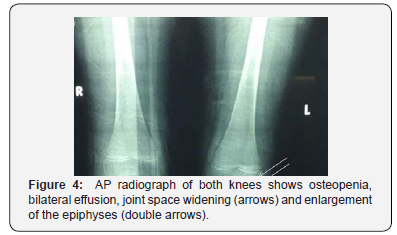

Cardiac ultrasound showed no abnormalities or effusion. Plain X-ray of both hands showed flexion at 3rd, 4th and 5th proximal interphalangeal joints (PIP) and distal interphalangeal joints (DIP) of right hand and flexion at DIP joint of the left 4th finger (Figure 3). Knees X-ray showed osteopenia, bilateral effusion, swelling of soft tissues, joint space widening, and epiphyseal widening of both knees (Figure 4). Pelvis X-ray showed short broad femoral neck, bilateral coxa vara and acetabulum lunate surface sclerosis (Figure 5). Knee ultrasound revealed large bilateral joint effusions.

Radiological appearances confirm the diagnosis of CACP. Knees X-ray showed osteopenia, bilateral effusion, swelling of soft tissues, joint space widening, and epiphyseal widening of both knees. Knee MRI image of the older sister, patient 2, showed intraosseous cysts inside the bone, without bone erosion [12].